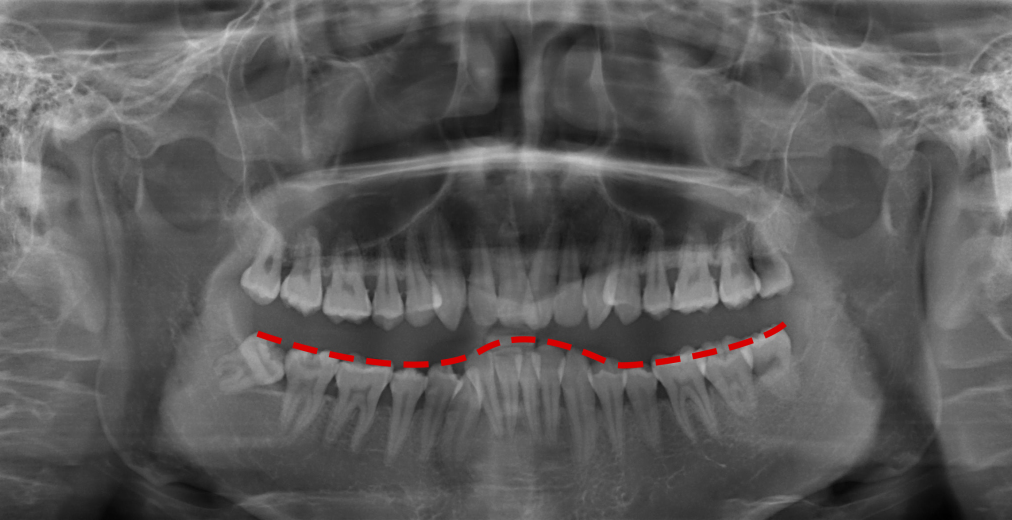

🔎牙周情况

通常来说,健康的牙槽骨的牙齿周围是被牙龈包裹住没有很大缝隙的,牙间缝隙较大而且是黑色阴影,牙齿整体比较长,多半是牙周炎,且牙槽骨情况也不好。

X光拍片为什么要等看牙为什么要拍片?非专业人士如何看懂自己的牙片!_https://www.jmylbn.com_新闻资讯_第12张

△正常情况下,牙槽骨高度位于牙根与牙冠的交界处下方一点(白色线标注位置)。